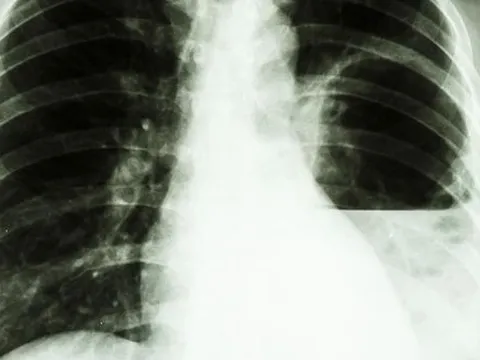

Whitmore là bệnh nhiễm trùng ở người và động vật do vi khuẩn Burkholderia pseudomallei gây ra.

Bệnh Whitmore có thể diễn biến nặng, tử vong, đặc biệt ở những người có bệnh nền như tiểu đường, bệnh gan, thận, phổi mạn tính, suy giảm miễn dịch.

Whitmore còn được mệnh danh là "kẻ bắt chước đại tài" vì triệu chứng gây ra khó nhận biết. Nhiều người được chẩn đoán khi đã muộn và không thể tránh khỏi cái chết.